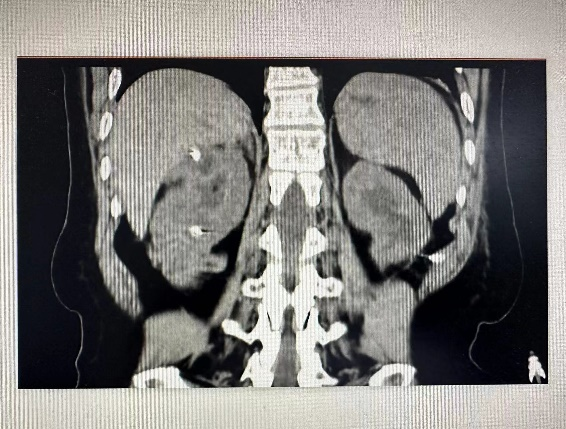

外四科皮生明主任查看患者,為避免感染及膿毒血癥進(jìn)一步加重,立即安排術(shù)前相關(guān)檢查及準(zhǔn)備,一切準(zhǔn)備就緒,急診行“雙側(cè)經(jīng)皮腎穿刺造瘺”術(shù),經(jīng)過(guò)1個(gè)多小時(shí)手術(shù)及時(shí)解決了患者可能出現(xiàn)的病情變化及并發(fā)癥,患者術(shù)后12小時(shí)各項(xiàng)感染指標(biāo)控制,腎功能改善,肌酐由術(shù)前264μmol/L降至114μmol/L。

(術(shù)前) (術(shù)后) 術(shù)后,張阿姨和家屬及時(shí)將5000元墊付住院費(fèi)還給了湯醫(yī)生,查房時(shí),張阿姨拉著醫(yī)生的手激動(dòng)的說(shuō):我們兩口子都不懂,要不是你們積極幫助,我怎么可能那么順利及時(shí)得到手術(shù),去哪里找這么好的醫(yī)生,太謝謝你們了,我們好好配合治療,聽(tīng)你們安排,就盼著早點(diǎn)恢復(fù)好回老家過(guò)年。 這只是外四科日常工作的縮影,全體醫(yī)護(hù)人員將患者的就醫(yī)感受,就醫(yī)體驗(yàn)牢記于心,力所能及為患者解決困難和問(wèn)題。